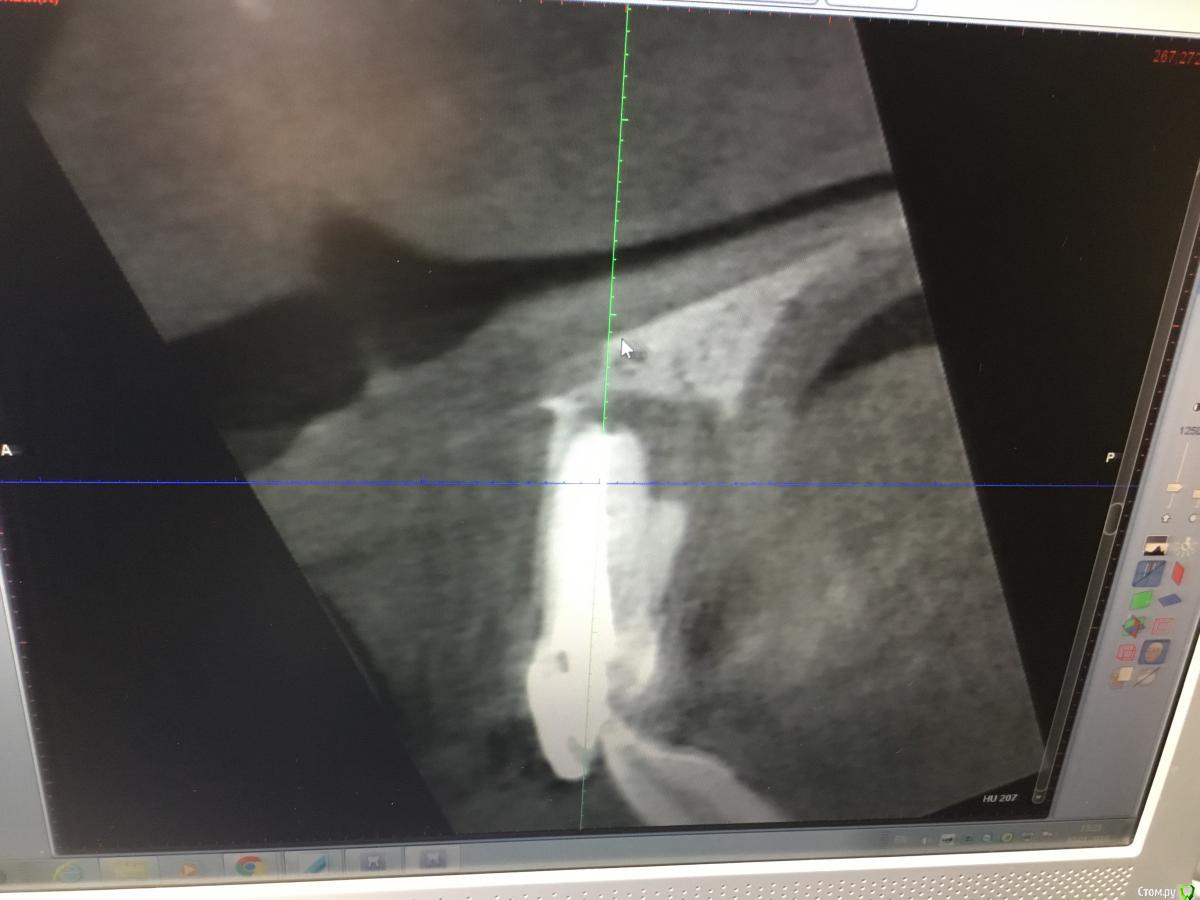

Zorrro Опубликовано 6 марта, 2016 Поделиться Опубликовано 6 марта, 2016 (изменено) Мой постоянный пациент привёл своего сынишку с жалобами на свищь на нёбе.Сделали кт и решили ,что вначале переберём каналы,а через пол года будем посмотреть куда нам двигаться дальше… Эстетика коронки на 11 вполне устраивала пациента,тем более он был уверен,что поставилимплант и вследствии коронку популярный доктор используя новейшие технологии и материалы,позволяющие не прибегать к устаревшим костным и ещё каким-то пластикам.запись к доктору уходила на пол года вперёд и молодой человек чудом втиснулся в этот плотный график,чтобы отхватить немножко и себе этих самых "новейших" технологий под нос. Фото ещё раз показывает,чтосамое главное в успехе частной практики это ВЕРА доктора в себя и то,что он делает.меня же коронка устраивала тем более,потому что переделывать её вместе с имплантом мне крайне не хотелось.обошлись комментарием про усиленную гигиену и регулярные наблюдения раз в пол года. итак занялись посильным трудом:отмыли 21 и 22,констрикция убежала за 50.02,остановились на 70.02 стальными файлами отступя 1мм,метапекс,через 2 недели irm и стекловолокно нафуджи+,филтек.договорились про контроль через пол года и коронки если всё ок. Ещё немного срезов до и преимущество кт перед прицельными снимкамиИ сразу после. Про коронки и корневой герметизм пациент не понял и решил оставить бломбы на месте. Изменено 6 марта, 2016 пользователем Zorrro 1 Ссылка на комментарий